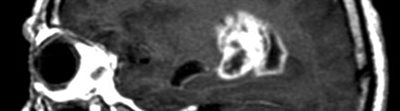

Brain scan